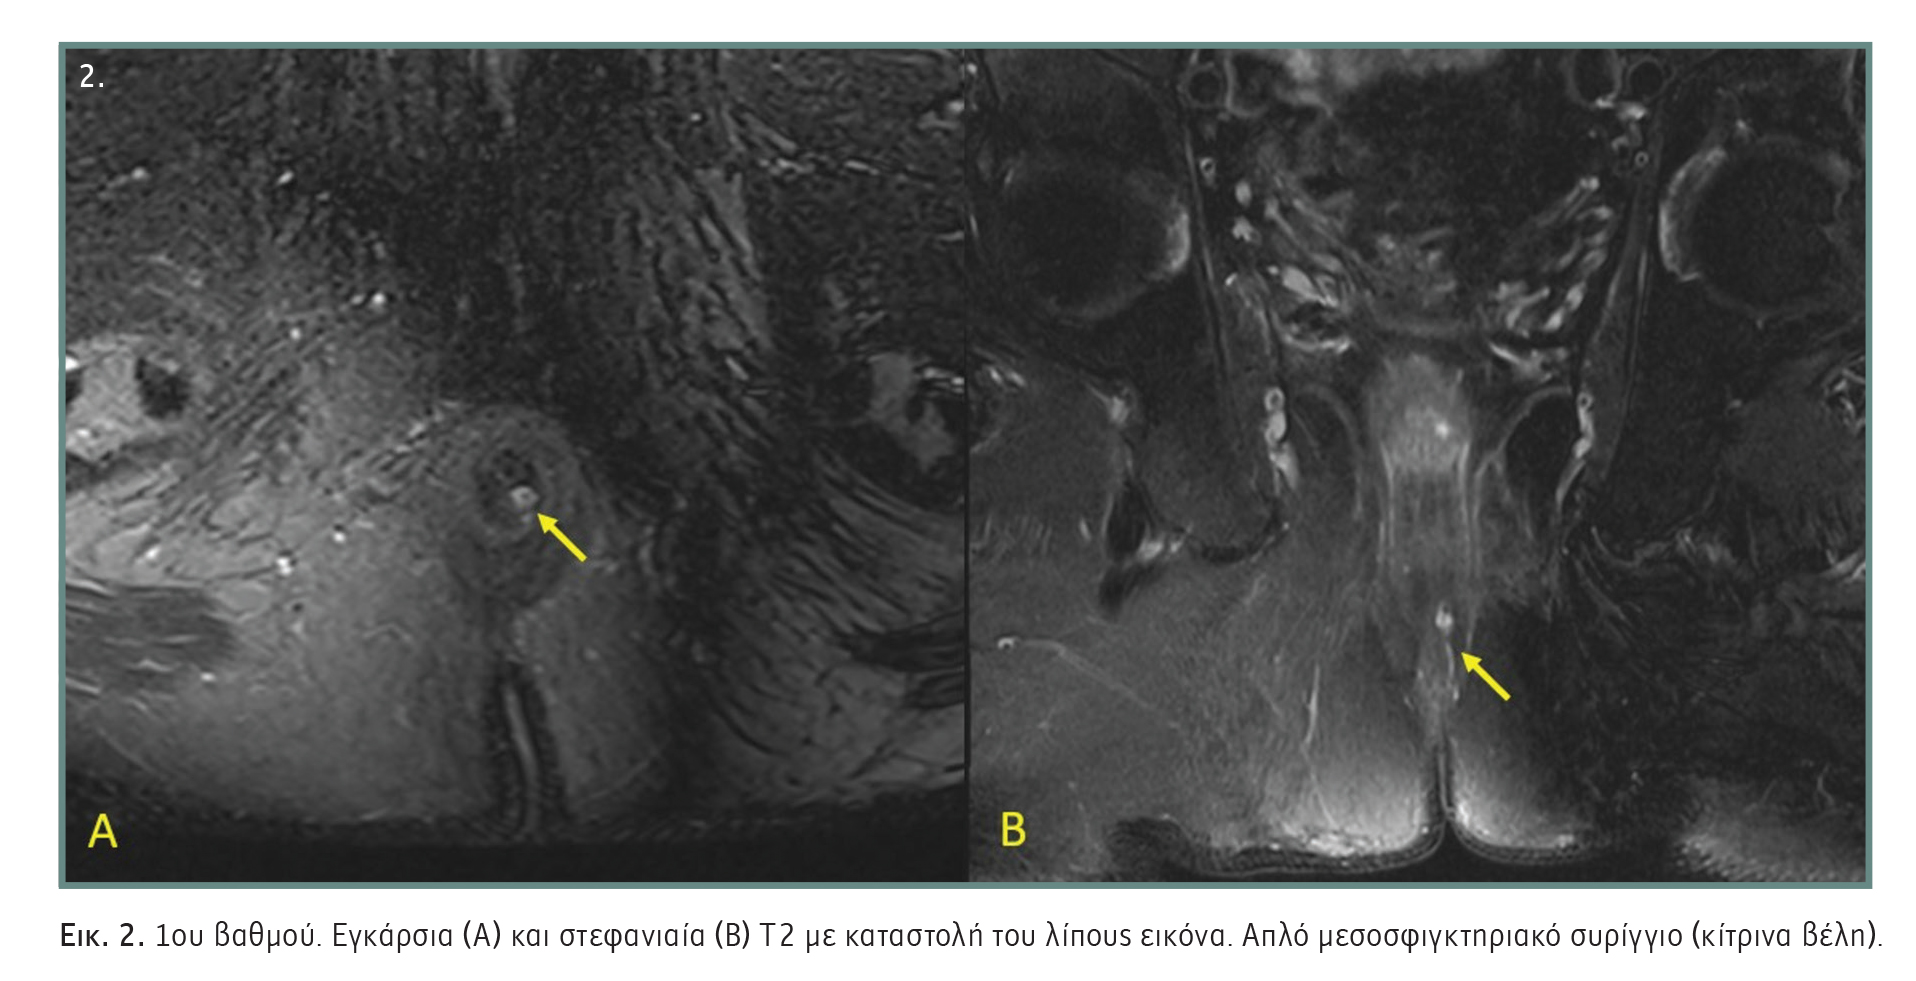

- 5ου βαθμού: Υπερανελκτήριο και διανελκτήριο συρίγγιο. Περιεδρικό συρίγγιο, το οποίο εκτείνεται πάνω από το επίπεδο εισόδου του ανελκτήρα μυός. Το υπερανελκτήριο συρίγγιο είναι παρόμοιο με το υπερσφιγκτηριακό και το διανελκτήριο με το εξωσφιγκτηριακό στην ταξινόμηση κατά Parks (Εικόνα 6).